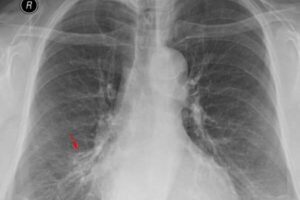

Первые признаки и симптомы пневмонии у детей

Пневмония чаще встречается у детей в возрасте от 3 до 10 месяцев, чем в других возрастных группах. Опасность заболевания у грудничков заключается в том, что воспаление развивается быстро (иногда в течение нескольких часов) и нарушается работа пищеварительной системы. Если инфекцию не лечить быстро, могут воспалиться другие органы, например мочеполовая система. Важно знать первые симптомы, чтобы …